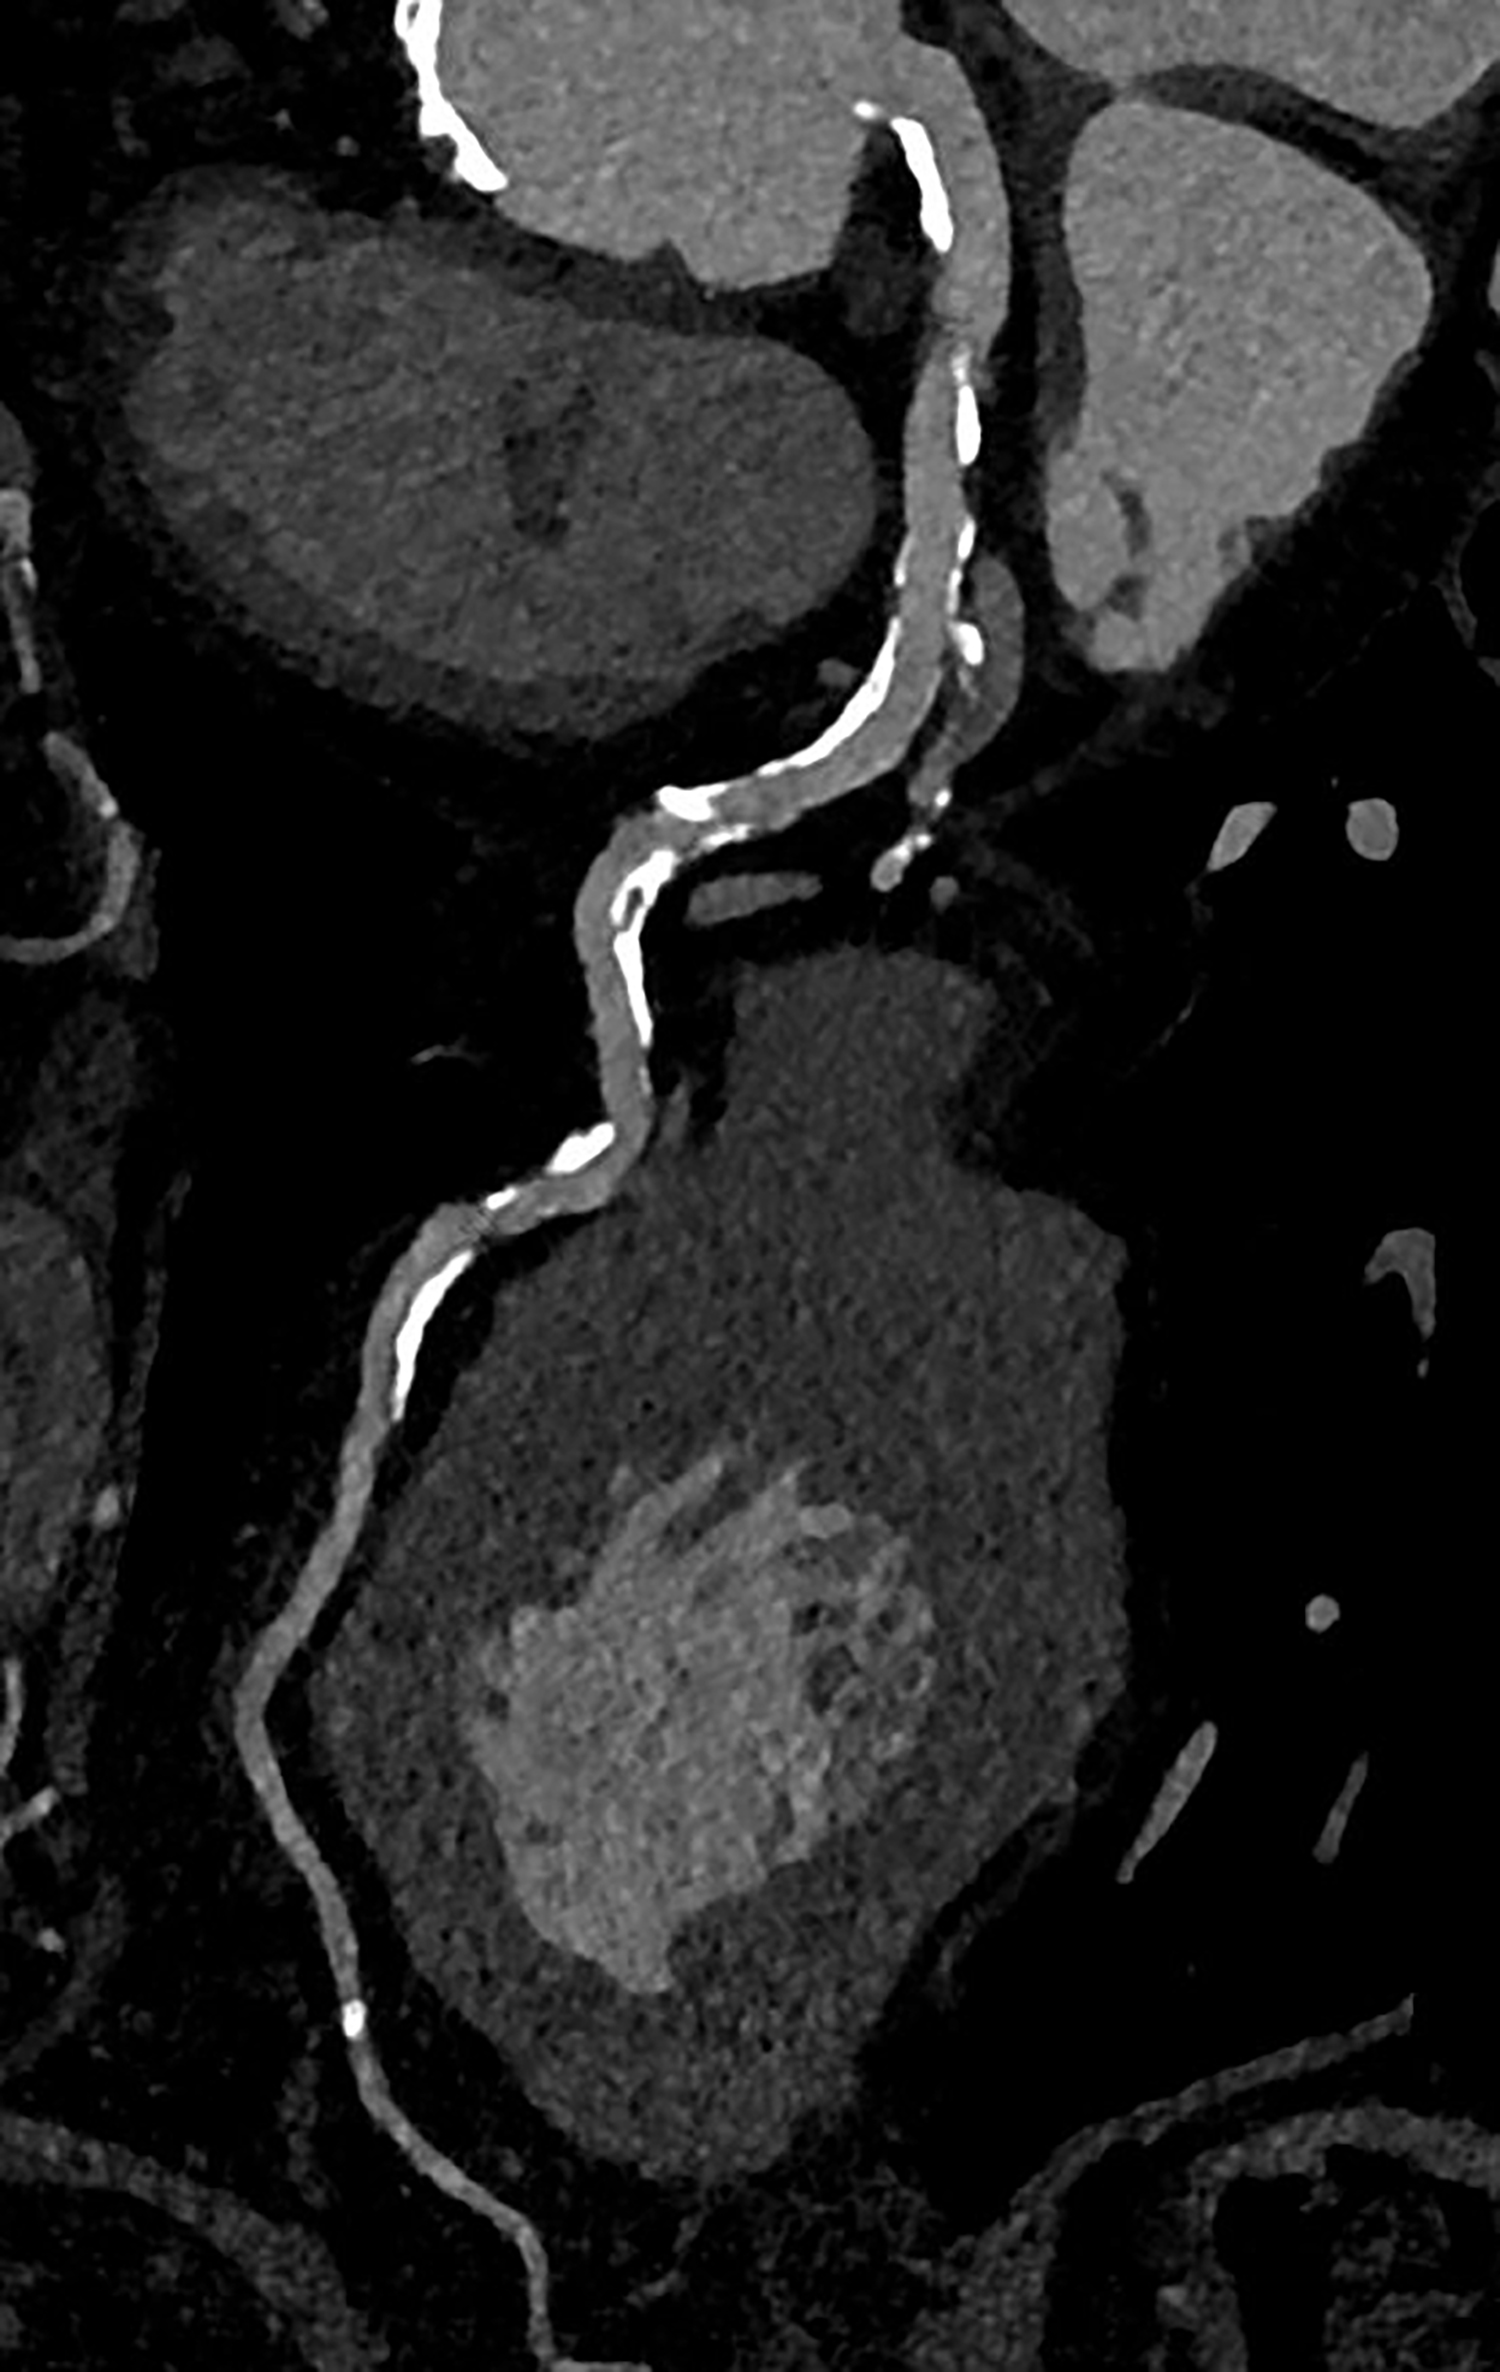

Die koronare CT-Angiographie eignet sich besonders gut zum Ausschluss einer koronaren Herzerkrankung bei Patient*innen mit niedrigem oder mittlerem Risiko für Veränderungen der Herzkranzgefäße. Bei Personen mit hohem Risiko gestaltete sich dies bislang aufgrund von häufig auftretenden koronaren Verkalkungen und Stents jedoch schwierig. Muhammad Taha Hagar, Erstautor der Studie und Arzt der Klinik für Diagnostische und Interventionelle Radiologie am Universitätsklinikum Freiburg erklärt: „In klassischen CT-Bildern erscheinen Verkalkungen der Herzkranzgefäße oft größer als sie tatsächlich sind. Dieser Effekt ist umso stärker, je größer die Verkalkung ist.“ Dadurch konnte es bislang zu einer Überbewertung von Verengungen und Plaques und in der Folge zu einer Überbehandlung kommen. Darum wurden diese Personen bislang schnell in den Herzkatheter überweisen oder in der Magnetresonanztomografie untersucht.

In der von Hagar und Kolleg*innen durchgeführten Studie wurden 68 Proband*innen mittels Photon-Counting-CT und einer invasiven Koronarangiografie als Referenzstandard untersucht. Die Patient*innen litten alle unter einer schweren Aortenklappenstenose, einer gängigen, aber ernsthaften Herzerkrankung, die den Blutfluss vom Herzen zur Aorta reduziert oder blockiert. Die Photon-Counting-CT-Untersuchung zeigte sich sehr genau in der Erkennung oder dem Ausschluss der koronaren Herzerkrankung. Auch wurde die Bildqualität in fast 80 Prozent als gut oder hervorragend bewertet.